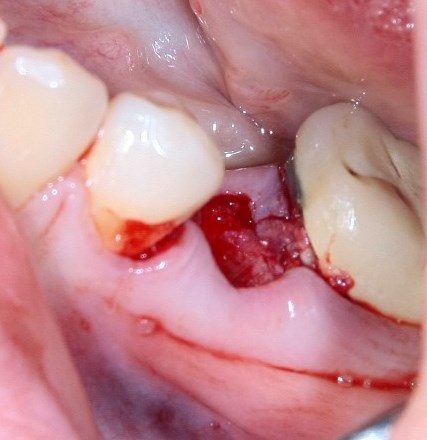

Немедленная имплантация — оптимальное решение в любой клинической ситуации